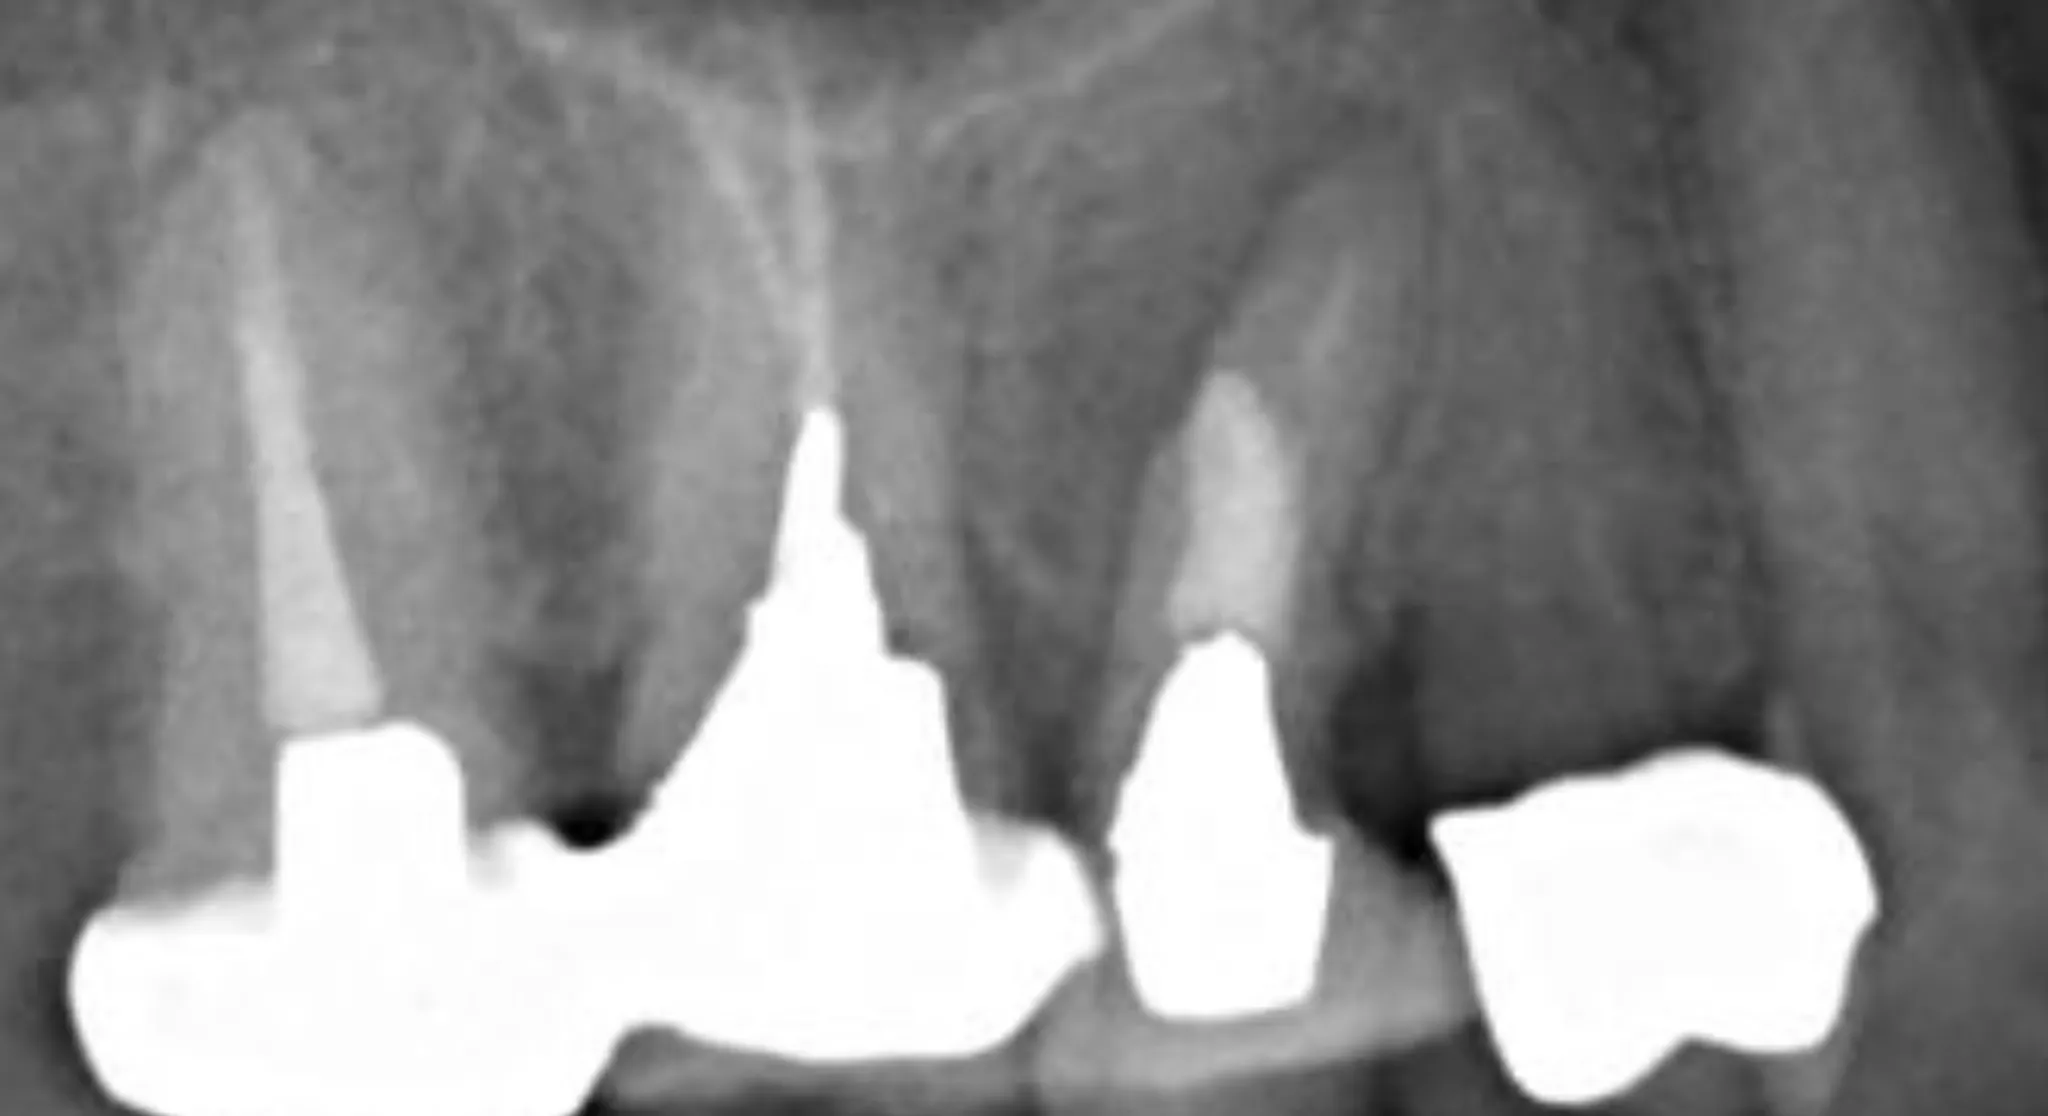

当院では、最新の技術を積極的に導入し、精度の高い治療を提供しています。

特に、すべての治療においてマイクロスコープを導入することで精密な治療を実現します。

最新技術の導入により治療の精度が向上し、再発のリスクを減らすことができるため、患者さんにとっての長期的な健康を守る重要な手段となっています。 -